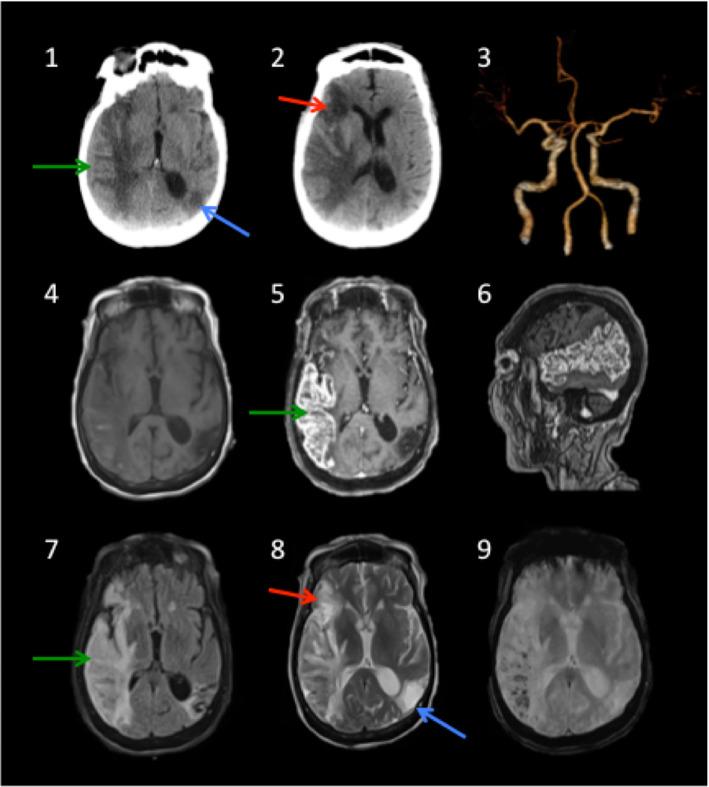

Coronavirus disease 2019 (COVID-19) is a highly infectious pandemic caused by a novel coronavirus called severe acute respiratory syndrome coronavirus 2 (SARS-CoV-2). It frequently presents with unremitting fever, hypoxemic respiratory failure, and systemic complications (e.g., gastrointestinal, renal, cardiac, and hepatic involvement), encephalopathy, and thrombotic events. The respiratory symptoms are similar to those accompanying other genetically related beta-coronaviruses (CoVs) such as severe acute respiratory syndrome CoV (SARS-CoV) and Middle East Respiratory Syndrome CoV (MERS-CoV). Hypoxemic respiratory symptoms can rapidly progress to Acute Respiratory Distress Syndrome (ARDS) and secondary hemophagocytic lymphohistiocytosis, leading to multi-organ system dysfunction syndrome. Severe cases are typically associated with aberrant and excessive inflammatory responses. These include significant systemic upregulation of cytokines, chemokines, and pro-inflammatory mediators, associated with increased acute-phase proteins (APPs) production such as hyperferritinemia and elevated C-reactive protein (CRP), as well as lymphocytopenia. The neurological complications of SARS-CoV-2 infection are high among those with severe and critical illnesses. This review highlights the central nervous system (CNS) complications associated with COVID-19 attributed to primary CNS involvement due to rare direct neuroinvasion and more commonly secondary CNS sequelae due to exuberant systemic innate-mediated hyper-inflammation. It also provides a theoretical integration of clinical and experimental data to elucidate the pathogenesis of these disorders. Specifically, how systemic hyper-inflammation provoked by maladaptive innate immunity may impair neurovascular endothelial function, disrupt BBB, activate CNS innate immune signaling pathways, and induce para-infectious autoimmunity, potentially contributing to the CNS complications associated with SARS-CoV-2 infection. Direct viral infection of the brain parenchyma causing encephalitis, possibly with concurrent neurovascular endotheliitis and CNS renin angiotensin system (RAS) dysregulation, is also reviewed.